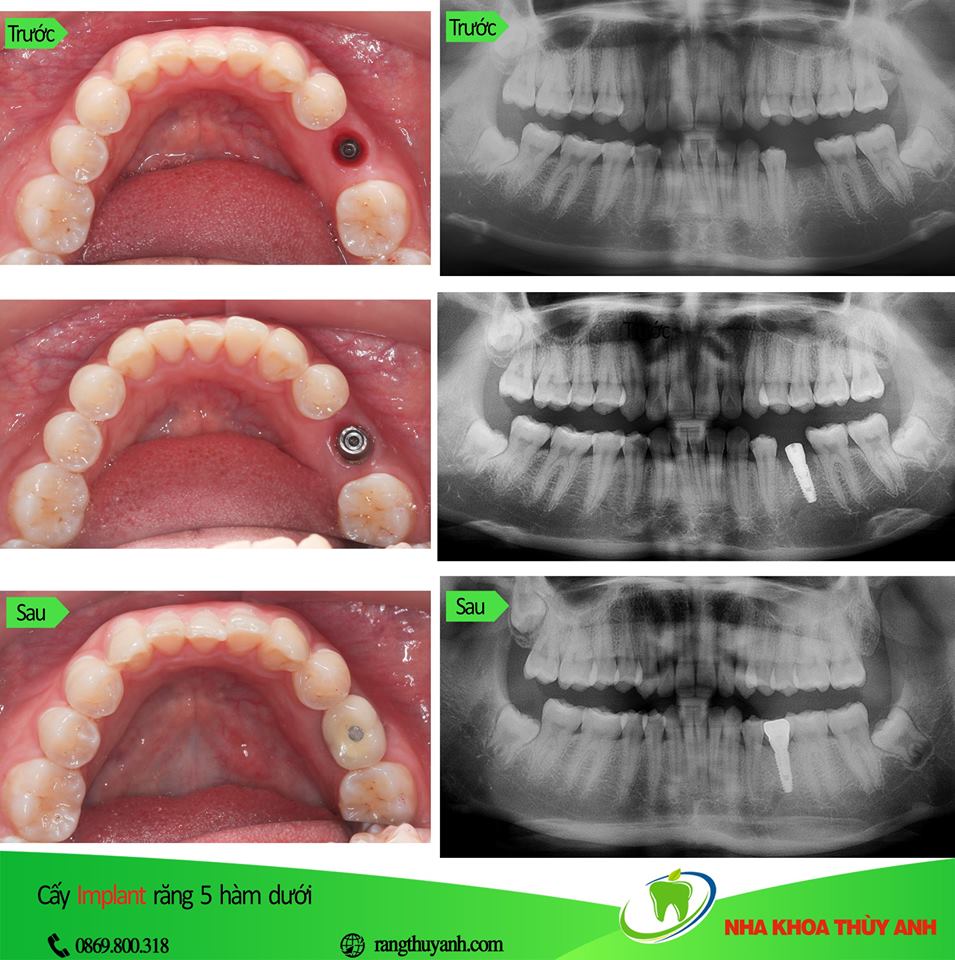

Với sự tiến bộ của y khoa nói chung và nha khoa nói riêng, ngày nay khi một chiếc răng bị sâu nha sĩ sẽ cố gắng điều trị để giữ nó lại và bảo vệ bằng 1 bụp răng sứ. Khi mất răng thì sẽ có phương pháp điều trị phục hình mà nổi bật hiện nay là phương pháp cắm chân răng nhân tạo implant.

Cấy implant là phương pháp trồng răng tốt nhất hiện nay. Implant gồm có 3 phần, phần thứ nhất là chân răng, được cấy thẳng vào xương hàm thay thế chân răng mất. Phần thứ 2 là trụ phục hình abutment đó là phần kết nối với chân răng và nhô lên khỏi lợi để răng sứ bọc lên đó. Phần thứ 3 là răng sứ, sẽ là 1 chụp sứ hoặc hàm giả gắn lên abutment.